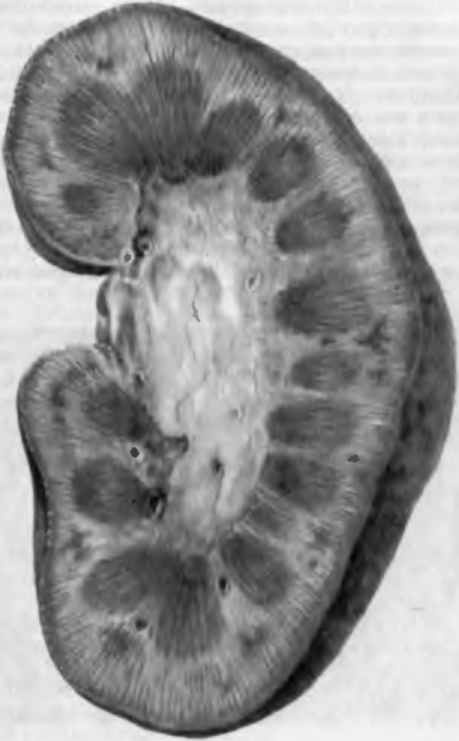

Симптомы подострого гломерулонефрита: фото и описание

Раздел: Визуальный дайджест